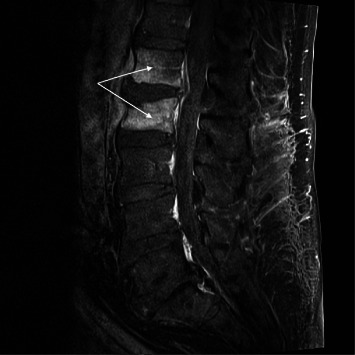

背景:尿气球菌是一种罕见的人类病原体,主要引起尿路感染、心内膜炎和菌血症。然而,它很少引起其他类型的感染,如脊柱炎。侵袭性尿支原体感染主要发生在有泌尿道疾病的老年男性中。实际发病率可能被低估了,因为气球菌生长在含二氧化碳的大气中,而尿液培养物通常不在这种环境中培养。有8例报告脊柱炎由尿单胞杆菌引起。材料和方法:我们报告了第9例发生在80岁的白人男性腰痛。患者有易感因素(糖尿病和泌尿外科手术史)。脊柱MRI显示脊椎椎间盘炎征象。两次针对椎间盘和腰肌的计算机断层引导活检没有诊断。10个血培养瓶中有一个培养出尿支原体。结果:在L2骨折恶化和不成功的经皮取样手术后,患者接受了T12至L4的手术稳定和多次活检。活检培养有尿气球菌。静脉滴注阿莫西林14天,口服左氧氟沙星3个月。结论:对于培养阴性的脊柱炎患者,尤其是有糖尿病和泌尿系统疾病的老年男性,应考虑尿支原体感染。

Background: Aerococcus urinae, a rare human pathogen, mainly causes urinary tract infection, endocarditis, and bacteremia. However, it is rarely the cause of other types of infection such as spondylodiscitis. Invasive A. urinae infection chiefly occurs in older men with underlying urinary tract disorders. The real incidence may be underestimated, as Aerococci grow in a CO2-containing atmosphere, and urine cultures are usually not incubated in this environment. There have been eight case reports of spondylodiscitis due to A. urinae. Material and Methods: We report a 9th case occurring in an 80-year-old Caucasian man with lower back pain. The patient had predisposing conditions (diabetes and a history of urological surgery). Spinal MRI showed signs of spondylodiscitis. Two computed tomography-guided biopsies targeting the intervertebral disc and psoas muscle were not diagnostic. One of 10 blood culture bottles grew A. urinae. Results: After worsening of an L2 fracture, and unsuccessful percutaneous sampling procedures, the patient underwent surgical stabilization of T12 to L4 with multiple biopsies. Biopsy cultures grew Aerococcus urinae. Amoxicillin was administered intravenously for 14 days, followed by oral levofloxacin for 3 months. Conclusion: A. urinae should be considered in spondylodiscitis with negative cultures, particularly in older men with diabetes and urological conditions.